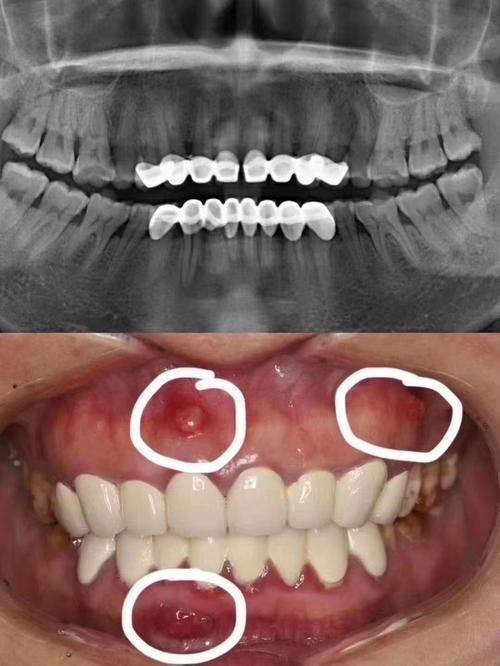

复杂牙体牙髓及根尖疾病治疗:能够精细诊断各类复杂的牙体牙髓病症,针对性开展相关诊疗操作,解决根尖疾病引发的疼痛、肿胀等问题,帮助患者保留天然牙齿,减轻病痛困扰。